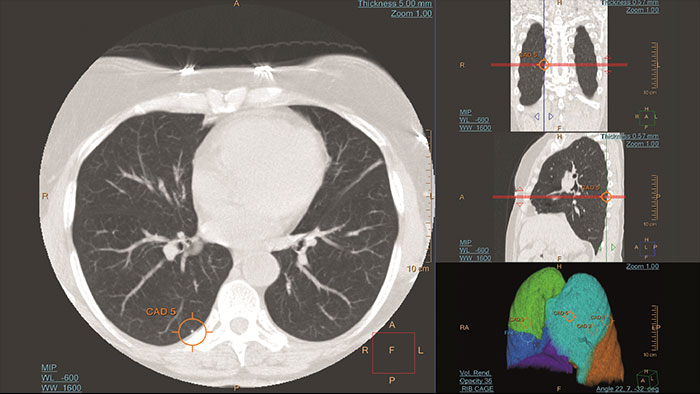

Automated computer aid for lung nodule detection

Artificial second reader to support the detection of lesions or nodules which may have been missed. It offers an automated process that identifies and marks regions of interest based on image features associated with lung nodules. It is intended for use as a second reader after an initial interpretation of the diagnostic image has been performed.